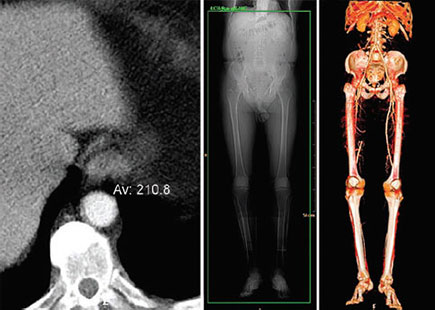

Ct Angiography Case07 Peripheral Arterial Occlusive Disease Paod Chronic Lower Limb Ischemia Youtube